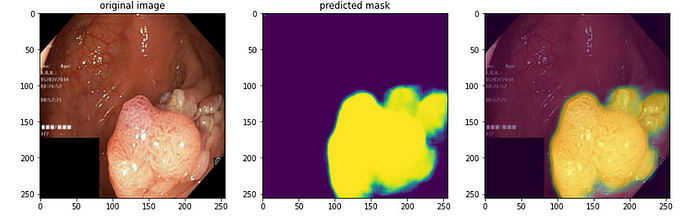

这个脚本从给定目录(images_path)获取图像文件。然后它将每张图像调整到给定的大小(256x256 像素)并保存在 numpy 数组(X)中。掩码也执行相同的过程。掩码也被调整到相同的大小并保存在 numpy 数组(y)中。结果,数组 X 包含处理后的图像,而数组 y 包含处理后的掩码。让我们看一个示例图像及其掩码:

iou_coef 的值在 0 和 1 之间,越接近 1,模型的性能越好。0.8496 的 IOU 值意味着模型的预测与实际分割掩码很好地重叠。这意味着模型的预测相当准确地识别了真实图像中的对象。现在,我们进入模型将在测试数据上进行预测的阶段:

让我们看看我们的结果: